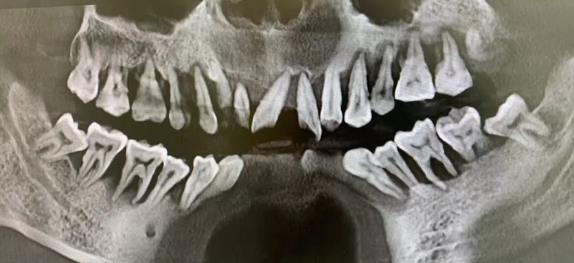

小谢该怎么办 小谢今天才4岁不到,正是花一样的季节!但小谢却无法像花朵一样绽放笑容,为什么呢?因为小谢还这么小,已经出现了左右脸不对称,右侧脸偏大,牙列拥挤的现象!...